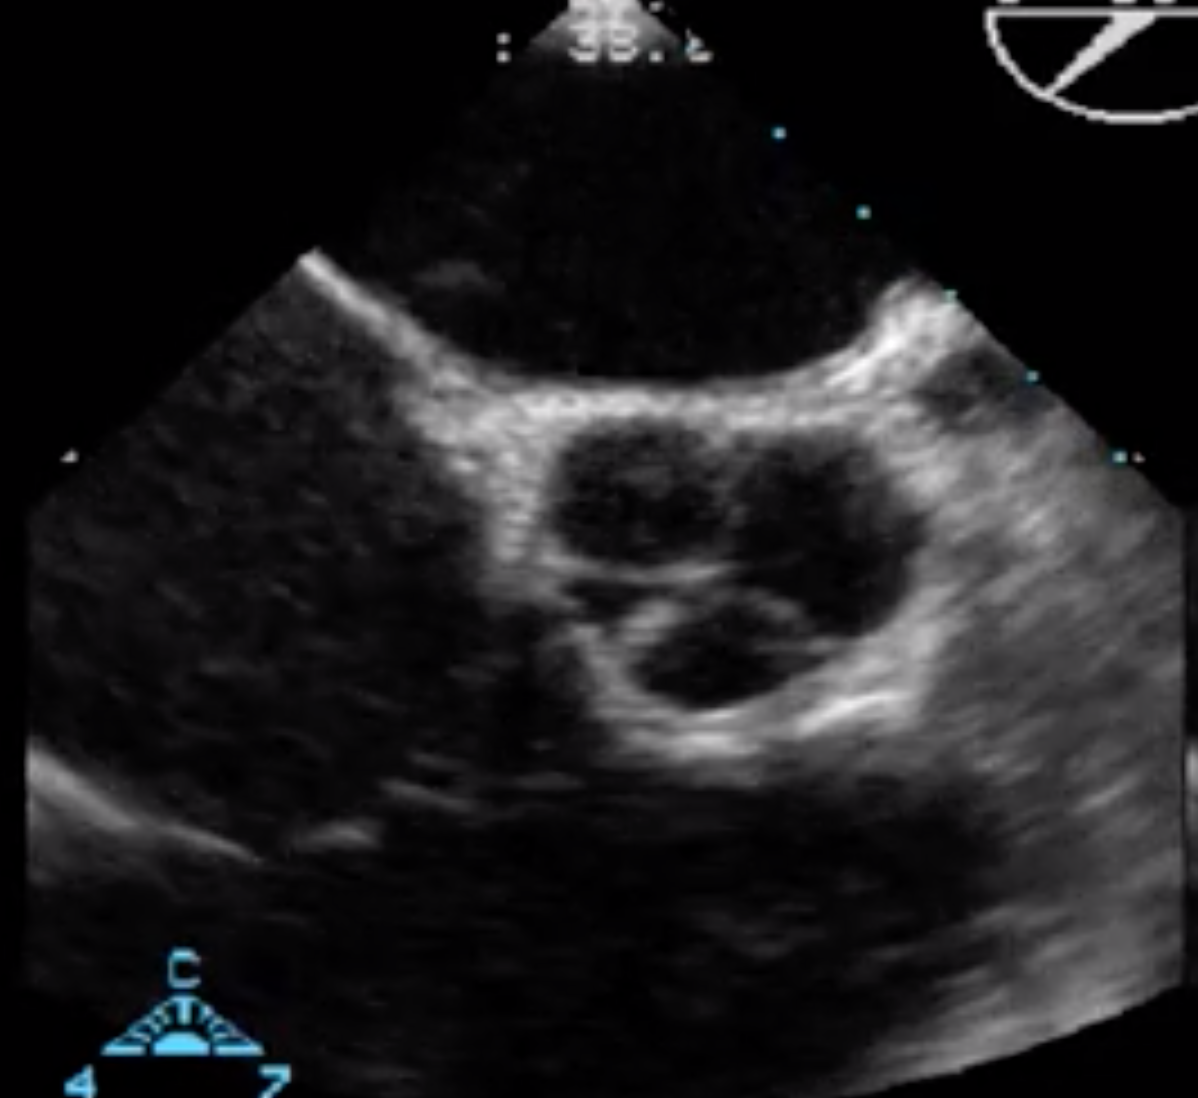

Label the Aortic Valve Cusps in the Aortic Valve Short Axis

Non-Coronary Cusp nearest to the interatrial septum (Does not have a coronary artery)

Left Coronary Cusp is NOT on the Right side

Right coronary cusp near the right heart at the bottom of the screen